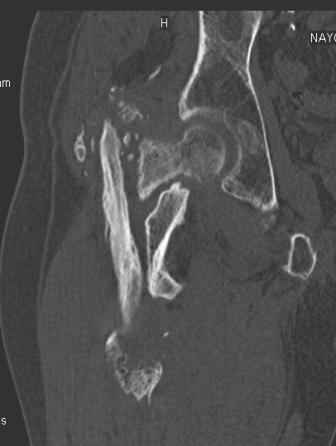

Больной Н. 44 года травма 1,5 года назад июнь 2008 года чрез-под вертельный перелом правого бедра. Во время лечения у больного развился алк. делирий, проводилось консервативное лечение перелома.

Беспокоят боли, укорочение конечности.Укорочение 3 см. Ногу поднимает, сгибание ограничено, ротационные движения в полном объеме.На КТ перелом сросся за счет костной мозоли.Что делать?

Уважаемый Глеб! Укорочение наверное побольше, да и наружно-ротационная установка скорее всего присутствует. Суставная щель прекрасная, головка живее всех живых. Ратую за подвертельную с латерализацией: исключает нарушение механической оси («исключает вальгус в коленe»), максимально удлиняет без натяжения m.iliacus. Для иллюстрации остеотомия-переделка (слава богу не автопеределка) у мужчины 65 лет.